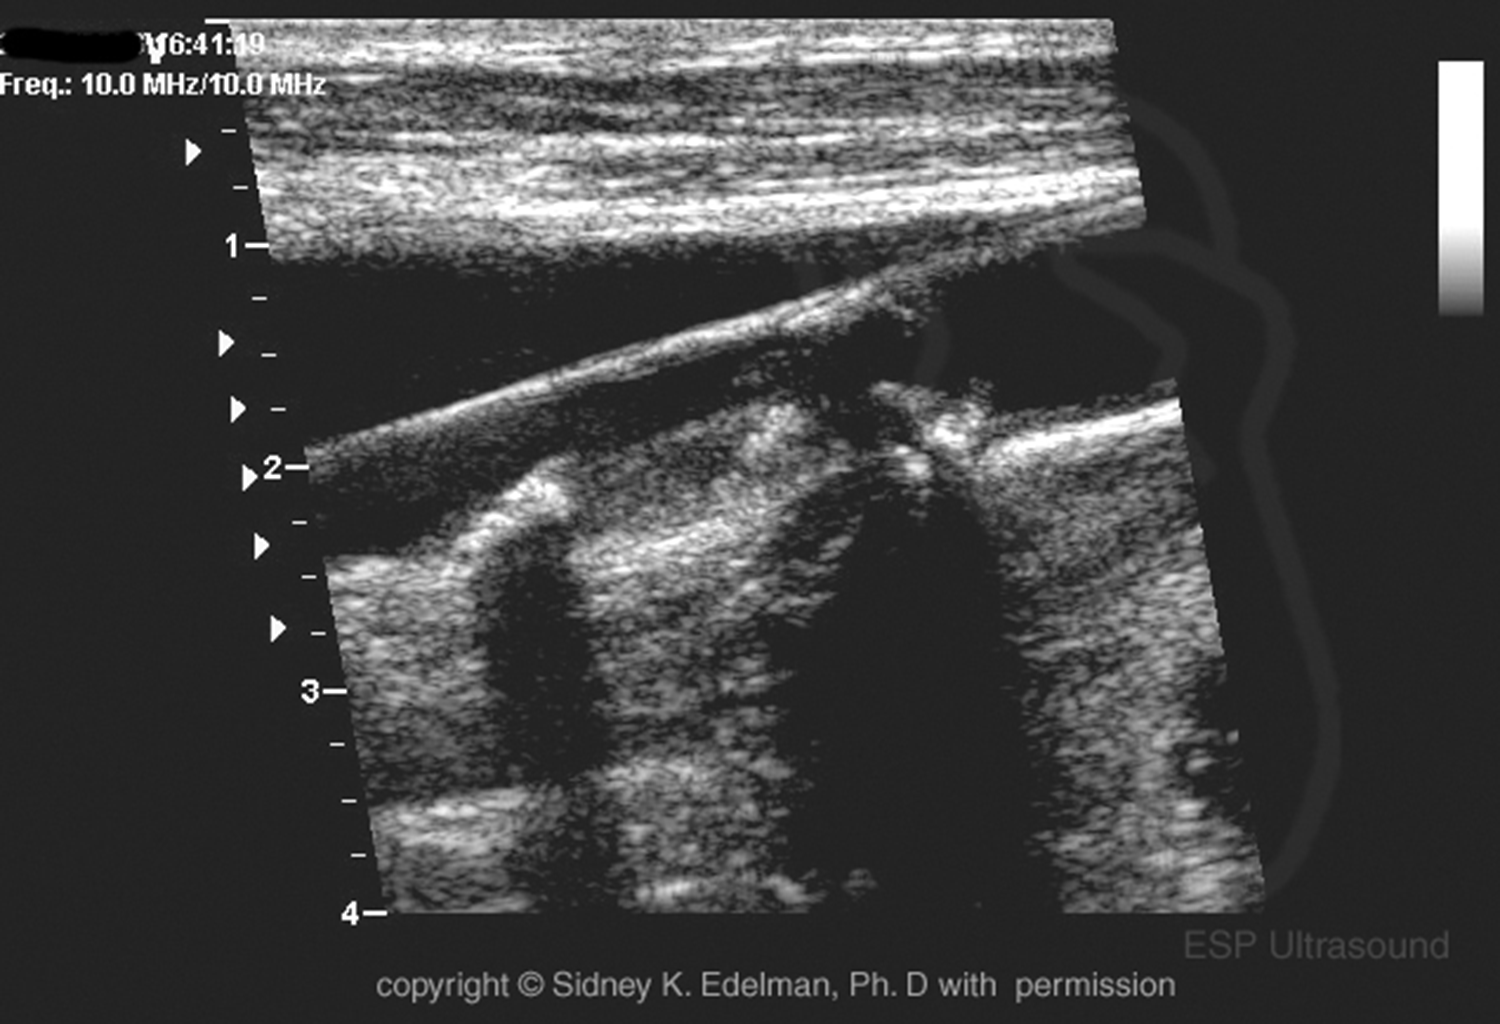

this is an example of damage to an

annular phased array transducer